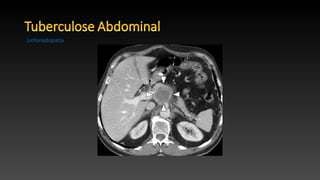

• O abdômen é o foco mais comum de tuberculose extrapulmonar,

com as vísceras sólidas sendo afetadas com maior freqüência.

• TC é o principal método para investigar tuberculose abdominal.

• O conhecimento de exames baritados, como enema, é importante

para evitar erros de diagnóstico nos casos em que a tuberculose não

é inicialmente suspeita.

• Manifestação mais comum da tuberculose abdominal observada em

55% -66% dos pacientes .

• Linfonodomegalia mesentérica e peripancreática, com múltiplos grupos

afetados simultaneamente.

• Linfadenite ocorre em 40% -60% dos pacientes linfonodomegalia com os

centros hipoatenuantes e um halo periférico hiperatenuantes,

característicos de necrose caseosa na TC.

• Essas massas de linfonodos não tendem a causar obstrução biliar,

gastrointestinal ou genito-urinário.

Linfonodopatia

• O abdômené o foco mais comum de tuberculose extrapulmonar, com as vísceras sólidas sendo afetadas com maior freqüência. • TC é o principal método para investigar tuberculose abdominal. • O conhecimento de exames baritados, como enema, é importante para evitar erros de diagnóstico nos casos em que a tuberculose não é inicialmente suspeita.

• Manifestação maiscomum da tuberculose abdominal observada em 55% -66% dos pacientes . • Linfonodomegalia mesentérica e peripancreática, com múltiplos grupos afetados simultaneamente. • Linfadenite ocorre em 40% -60% dos pacientes linfonodomegalia com os centros hipoatenuantes e um halo periférico hiperatenuantes, característicos de necrose caseosa na TC. • Essas massas de linfonodos não tendem a causar obstrução biliar, gastrointestinal ou genito-urinário. Linfonodopatia